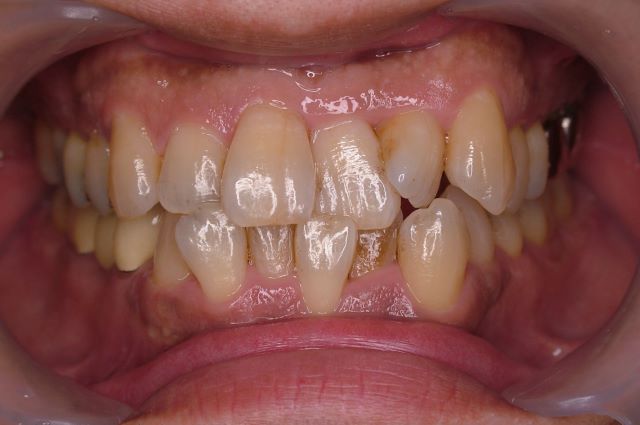

治療前

治療後

前方に飛び出した前歯を、白く形の良いセラミックで歯の向きまでいっぺんに治しました。この症例について、詳しくはこちらをご覧ください。